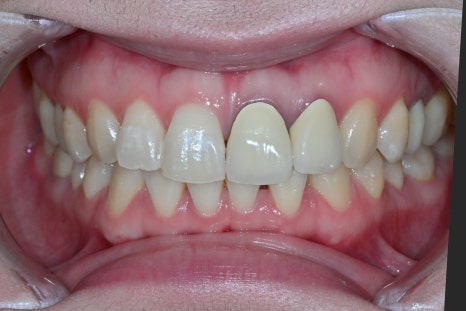

치료 전, 후 비교

<BEFORE>

<AFTER>

초진 내원 당시

환자분은 기존 크라운이 변색되고

잇몸과의 경계도 자연스럽지 않아

일상적인 대화나 사진 촬영에서

항상 신경을 쓰고 있었던 상태였습니다.